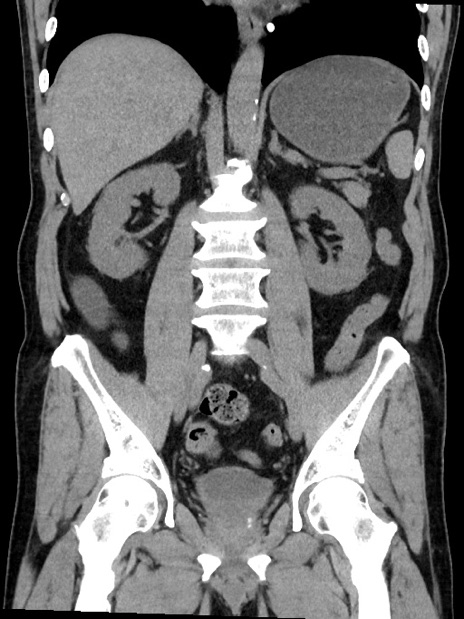

症例35(冠状断像)

【症例】70歳代 男性

【主訴】腹部膨満、嘔吐

【現病歴】昨日より腹部膨満感出現。本日増悪し、仙痛出現。嘔吐あり、受診。

【既往歴】糖尿病、胆摘後

【身体所見】BP 149/80mmHg、HR 74/min、BT 35.9℃、腹部:膨満、軟、圧痛なし。腸雑音減弱あり。上腹部正中切開瘢痕あり。

【データ】WBC 13500、CRP 1.72